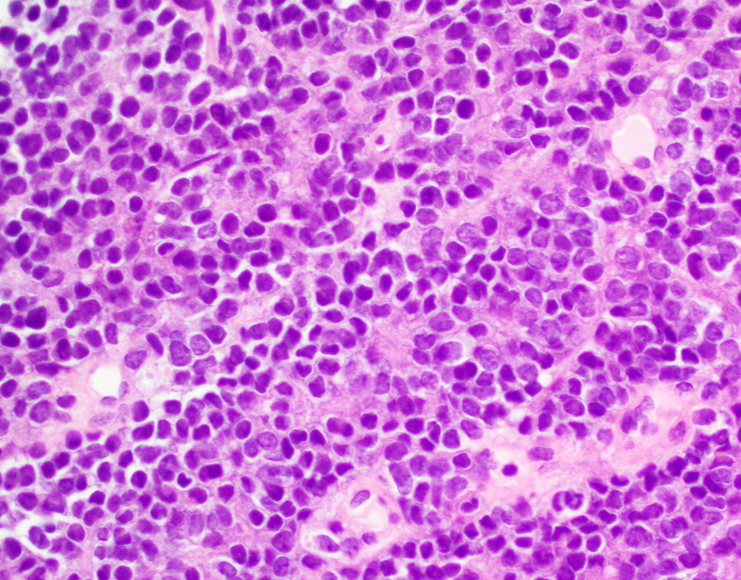

Microscopic (histologic) description

- Classical Ewing sarcoma (Virchows Arch 2009;455:397)

- Uniform small round cells

- Tumor cells 1 - 2x size of lymphocytes

- Round nuclei

- Finely stippled chromatin

- Inconspicuous nucleoli

- Scant clear to eosinophilic cytoplasm

- Indistinct cytoplasmic membranes

- Sheet-like growth pattern

Microscopic (histologic) images